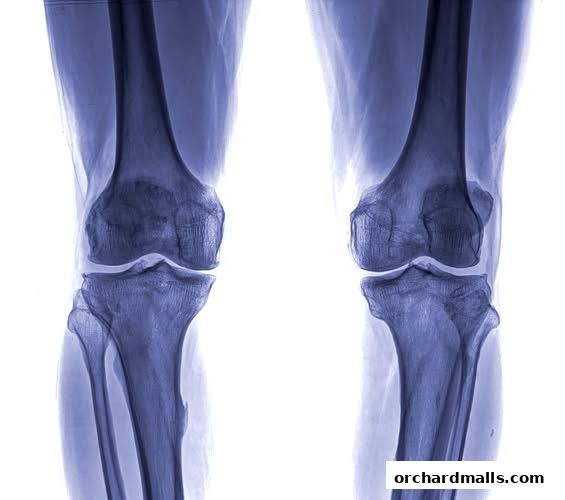

X-ray image of two human knees, showing bones and joints.